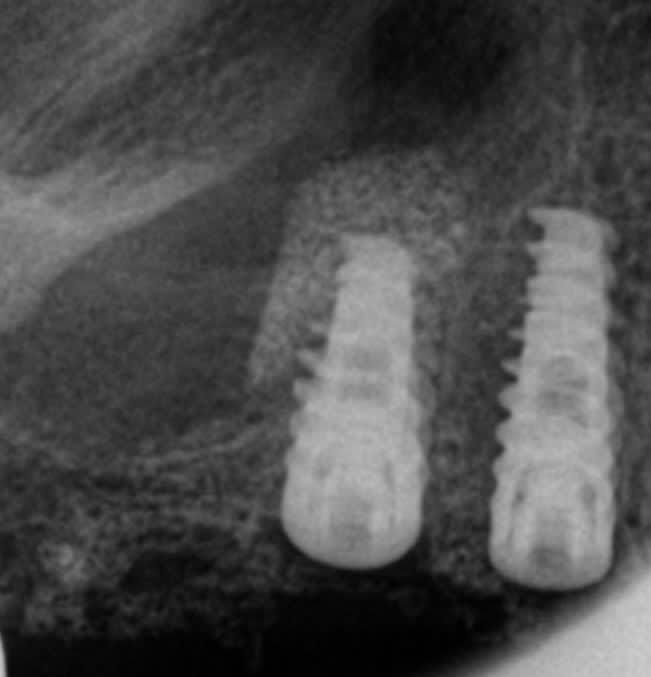

Une autre possibilite:Vous avez une idee du procede utilise?

On commence avec un plancher sinusien de 4.5 mm,On pose un implant de 4,2 sur 10 mm,dans la meme seance.(rx jour 0)